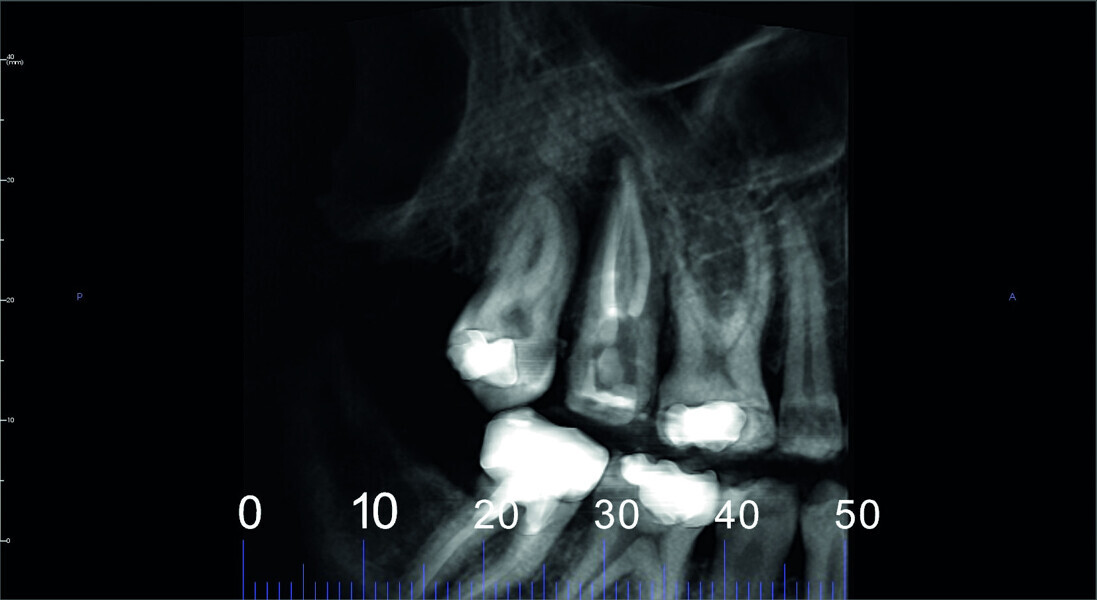

Fig. 5: Pre-op CBCT scan, sections.